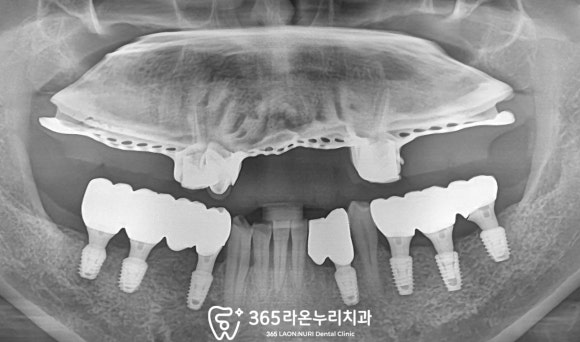

아래쪽 implant를 식립을 먼저 했습니다.

섬세하고 세밀하게 시술한 결과로

픽스처의 뱡향,깊이, 거리, 간격이

모두 일정하게

식립 된 것을 볼 수 있는데요,

송탄역 치과 365라온누리에서도

그간 쌓은 임상경험과 실력으로

장기적인 예후까지 고려한

최선의 진료만 해드릴 것을 약속드립니다.^^

의치와 implnat 모두 적응이 끝나고

불편한 것이 없으신지 체크해서

보철을 올려드렸는데요,

사진을 보니 전에 환경과

비교하기 힘들 정도로

좋아졌네요.